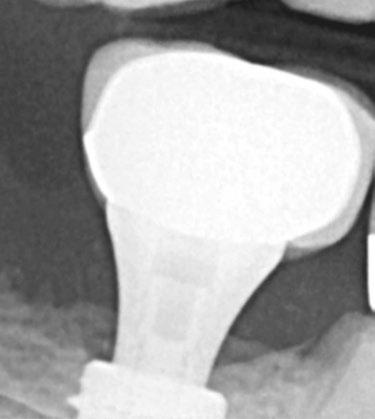

B A

1A. 1B. 2.

Figures 1A–2: 1A. The DSST generate a gentle and progressive vertical and horizontal bone compaction that enhances initial implant stability regardless of the bone type or quality. This preserves the vascularity of the osteotomy while maintaining the peri-implant marginal bone and soft-tissue. 1B. The ULT implant RCN (A) preserves a ring of marginal bone reducing stress on the crestal cortical bone. This prevents undesired vascular compression while preserving the peri-implant soft tissue. The platform switching (B), has a smaller diameter implant-abutment connection. This leaves space for the biologic width that limits bone resorption while stabilizing the soft tissue that ensures excellent papillary esthetics. The micro-grooves (A) provide mechan ical stimulus that helps preserve marginal bone, increase the surface area of the implant and the ability of an implant to resist axial loads. 2. The ULT implant bone platform switching preserves a ring of marginal bone reducing stress on the crestal cortical bone. This prevents undesired vascular compres sion while preserving the peri-implant soft tissue

Selection of the implant

Selection of the implant may have an effect on the overall clinical success, especially when immediate loading is required. As previously mentioned, thread design on the implant has an effect on initial stability and is correlated to bone density at time of placement. The Ditron Ultimate Precision Implant (ULT™) is designed with double stressless sharp threads (DSST), which gen erate gentle progressive vertical and horizontal bone compaction upon insertion into the osteotomy (Figure 1A). This enhances initial implant stability regardless of the quality of bone present while preserving the bone vascularity.7

Maintenance of the crestal bone is important to the long-term success of the implant. Under function, the majority of loading occurs at the crestal portion of the implant.8 So, the thicker this bone is around the implant, the better the load handling and preservation of this critical bone over time. Frequently, the thin buccal crestal aspect of bone adjacent to the implant resorbs, which may contribute to soft tissue recession and resultant esthetic compromise. Given time, this may progress to peri-im plantitis and compromise the health of the implant. So, the thicker the bone is at crest on the buccal/palatal dimension and between implants or the implant and adjacent natural teeth, the easier it is to preserve that critical crestal bone long-term.9

With this in mind, the ULT implant is designed with a slight platform switch at bone level or slightly subcrestal upon place ment. But in addition, the reverse concave neck (RCN) provides what has been termed bone platform switching,10 a narrowed concave neck strategy to preserve additional marginal bone beyond the platform switch (Figure 1B). Enhanced bone volume at the cervical not only helps provide for greater resistance to bone resorption, but also reduces overall stress on the crestal cortex (Figure 2). Less titanium at the crest also helps to prevent removal of delicate marginal and subpapillary bone, providing the vascularity necessary for preservation of the peri-implant soft tissue.10